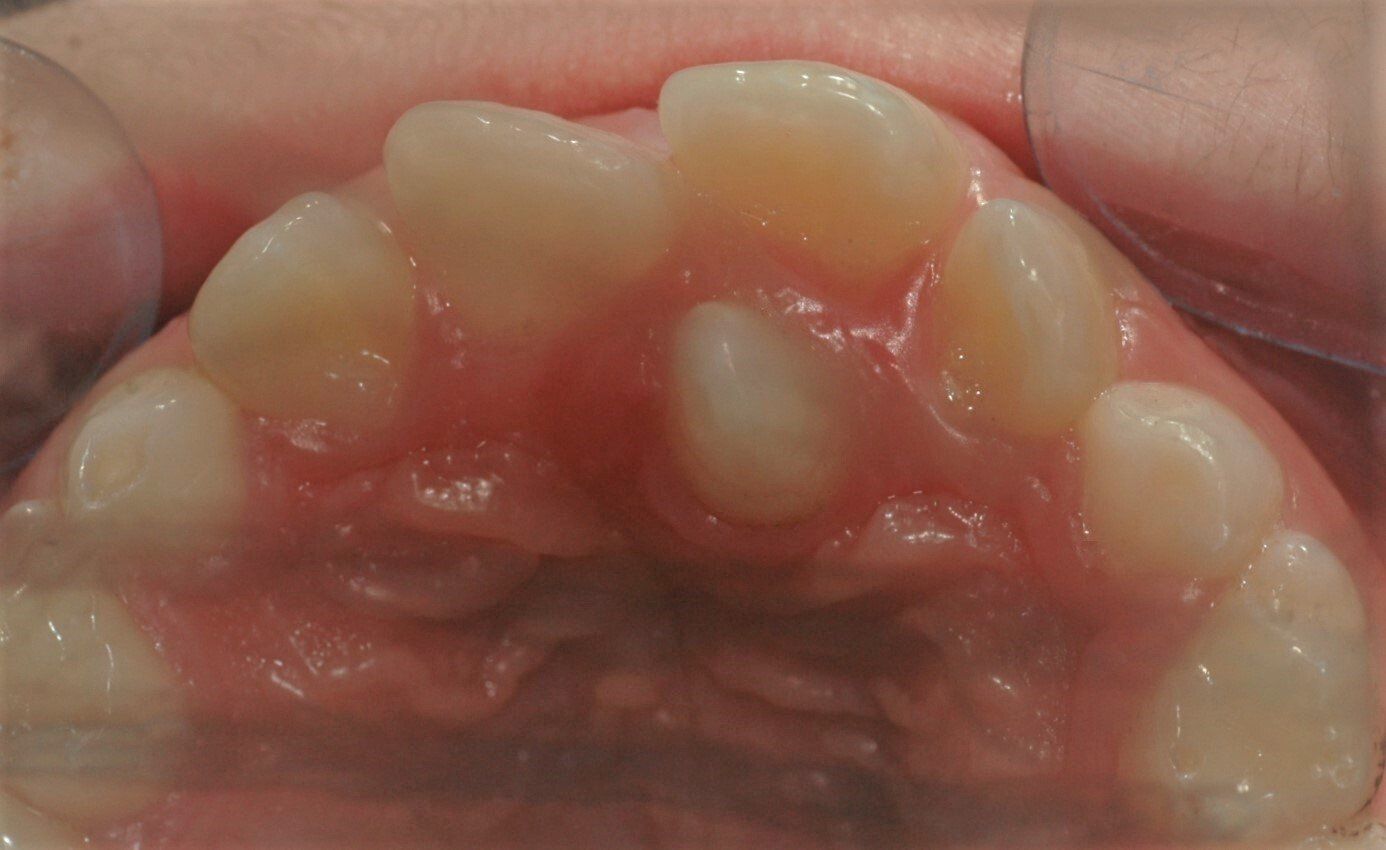

Überzähliger Zahn, der am Gaumen durchgebrochen ist. Er hat zur Schiefstellung der regulären Frontzähne geführt.

Überzähliger Zahn im Oberkiefer; es handelt sich histologisch um einen bleibenden Zahn. In dieser mittigen Lage spricht man von einem "Mesiodens". Der Zahn wurde entfernt und der Zahnwechsel konnte weiter normal ablaufen.